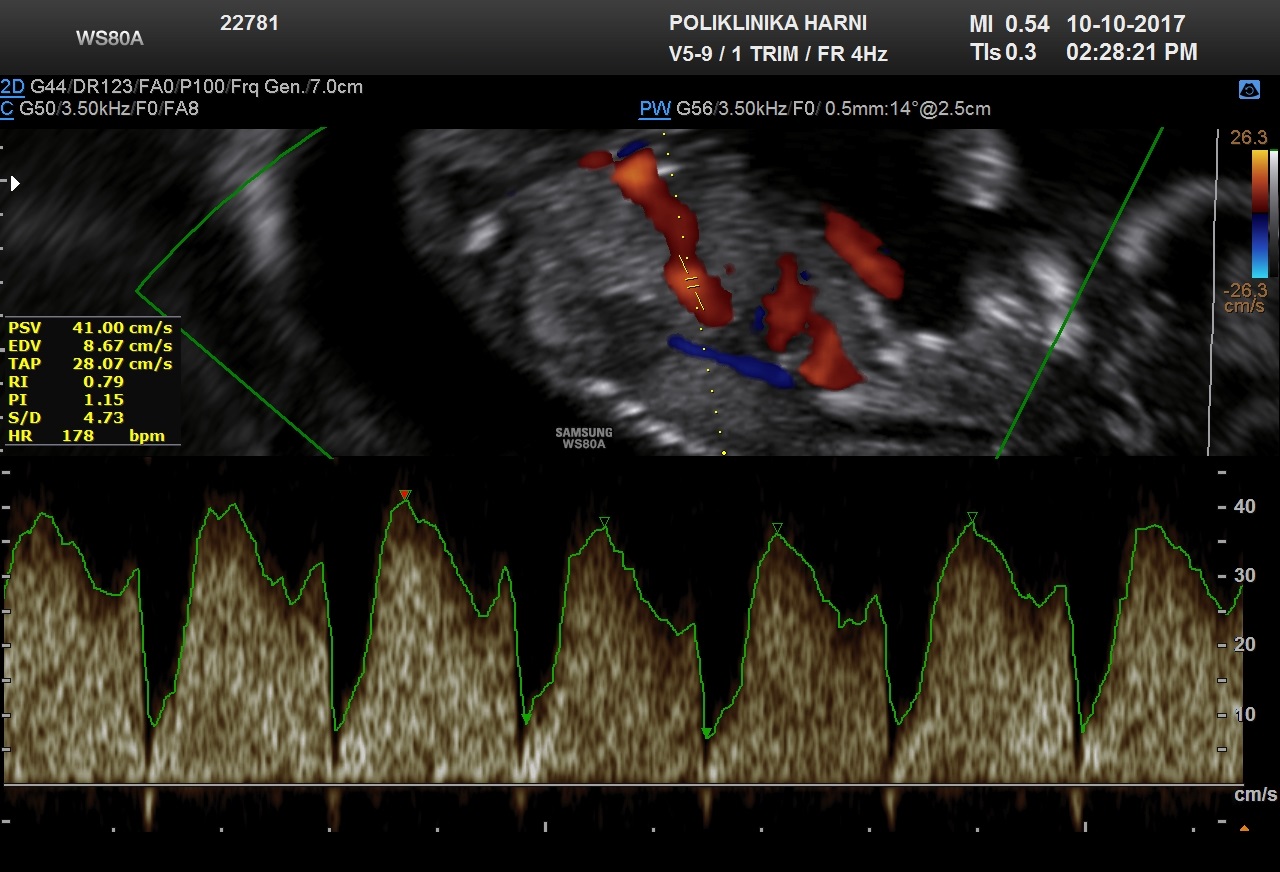

Kriteriji za procjenu protoka kroz duktus venozus

Za procjenu protoka kroz duktus venozus gestacija treba biti 11 + 0 do 13 + 6 tjedana, a CRL 45-84 mm. Fetus se ne smije kretati.

Povećanje slike treba biti takvo da prsni koš i trbuh fetusa zauzimaju čitav ekran.

Treba dobiti desni mid sagitalni prikaz trupa fetusa.

Color doppler treba koristiti kako bi se prikazala vena umbilikalis, duktus venosus i fetalno srce.

Pulsni dopplerski gate treba biti mali (0,5-1,0 mm) kako bi se izbjeglo onečišćenje iz susjednih vena i trebao bi biti postavljen u žućkastom spektru protoka.

Kut insonacije bi trebao biti manji od 30 stupnjeva.

Filtar treba postaviti na nisku frekvenciju (50-70 Hz) kako bi se omogućila vizualizacija cijelog valnog oblika.

Brzina pomicanja bi trebala biti velika (2-3 cm / s) tako da se valovi prošire za bolju procjenu a-vala.

Gate: 0,5-1 mm

Low filter: 50 Hz

Sweep speed: 2cm / s

Normalan i nenormalan protok

Protok krvi u duktusu ima karakterističan oblik vala:

- Velika brzina tijekom ventrikularne sistole (S-val) i dijastole (D-val).

- Pozitivan protok tijekom atrijske kontrakcije (a-val).

Kvalitativna procjena protoka krvi kroz duktus venosus temelji se na pojavi a-vala:

- Pozitivno ili odsutno (normalno).

- Obrnuto (nenormalno).